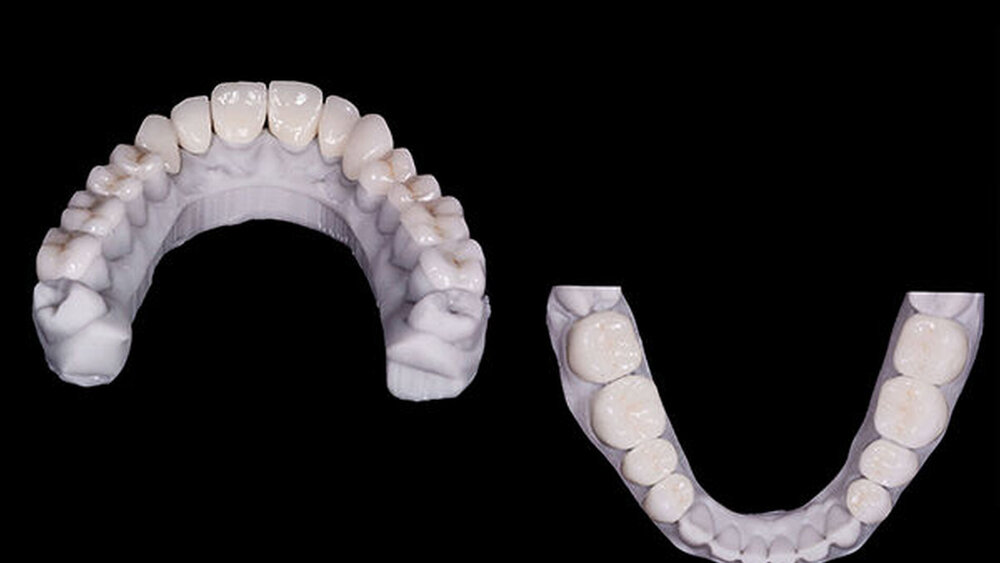

2017 kehrte der Patient wieder, um die Behandlung wiederaufzunehmen (Abb. 7) und ein neuer intraoraler Scan (Carestream 3600) wurde durchgeführt. Ein neues Mock-up für die Zahnpräparation wurde unter Verwendung einer vakuumgeformten Matrize (V-print Ortho clear; VOCO) mit einem 3D-Drucker (SolFlex; VOCO) aus Bis-Acryl (Structur; VOCO) gedruckt. Ausgehend vom Mock-up, wurden die Pfeilerzähne minimal präpariert (Abb. 8). Die alten Präparationen der Zähne im zweiten Sextanten wurden erhalten, die oberen Seitenzähne. Ein neuer intraoraler Scan wurde erstellt. Die Informationen wurden an das DSD-Labor übermittelt (Abb. 9), das daraus eine STL-Datei mit virtuellen Modellen erstellte, die im Labor (Anatomic Lab) gefertigt wurden. Diese 3D-Modelle (V-Print-Modell; VOCO) wurden in einem 3D-Drucker (SolFlex 650; VOCO) erstellt.

Finale Versorgung

Die endgültigen Veneers und Kronen wurden mit der Konstruktionssoftware „Ceramill mind“ (Amann Girrbach) digital vorbereitet und in einer Fräsmaschine (Ceramill Motion 2, Amann Girrbach) aus maschinell bearbeitbaren Lithiumdisilikat-Keramikblöcken (VITA BLOCS TriLuxe forte für Ceramill Motion 2, Amann Girrbach) gefertigt (Abb. 10). Nach der Bestätigung des Randschlusses und der optischen Eigenschaften bei einem probeweisen Einsetzen wurde ein Lippen-Wangen-Halter (OptraGate, Ivoclar Vivadent) angelegt.